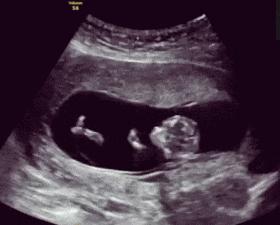

胎动,顾名思义就是胎儿在妈妈子宫里活动,比如伸手、蹬腿、翻身、打嗝等,触碰激烈时,妈妈就会有所感觉。一般而言,大多数的孕妇在孕4月开始感受到第一次胎动。